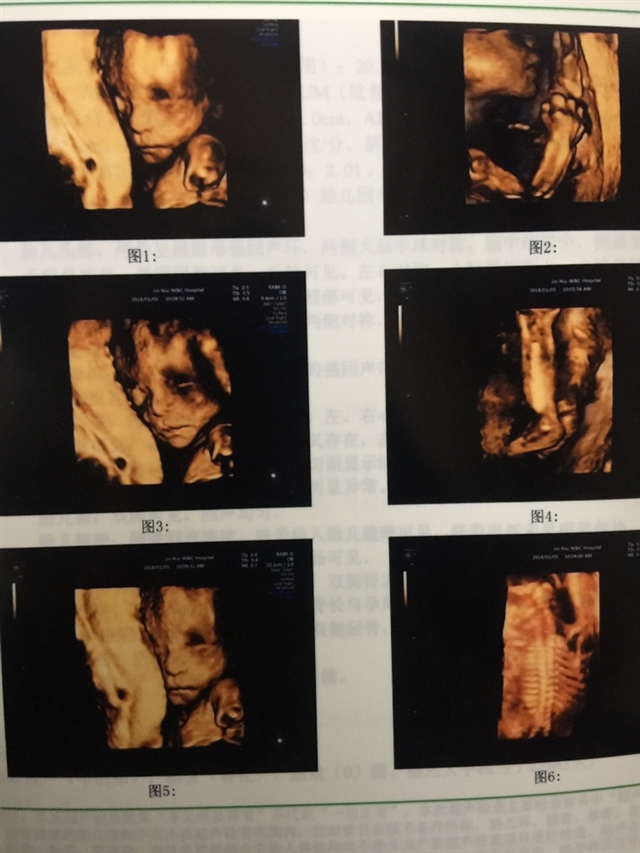

孕22周+0天

恭喜恭喜,接健康宝宝,接四维顺利通过!